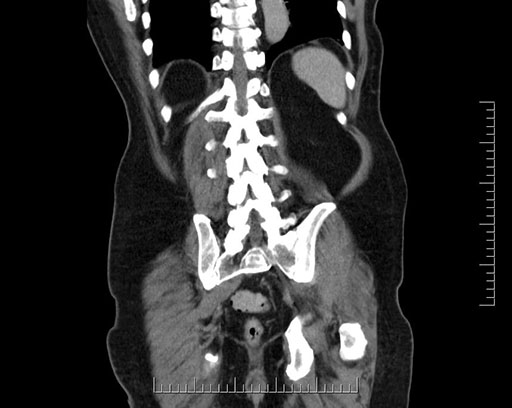

Whipple (pancreaticoduodenectomy) [case 7]

Imaging Analysis

Look through the patient's CT scan to identify any areas of concern for the necessary procedure.

Coronal - stented